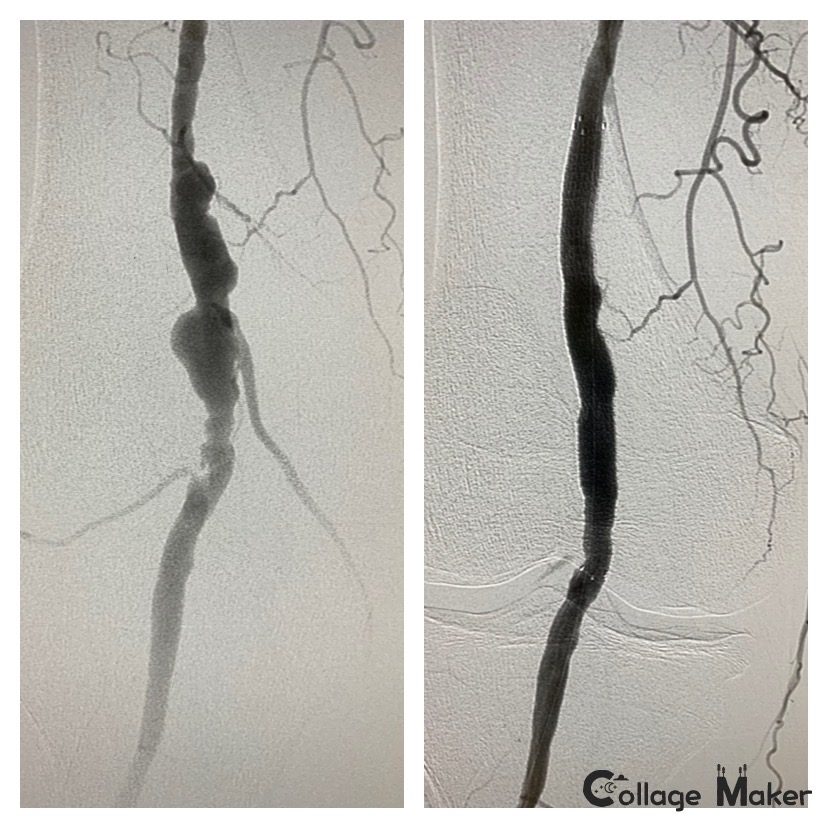

Arterial Aneurysms

Case of the Day – Arterial Aneurysms

Arterial aneurysms in the peripheral vessels are not benign, they can be a source of major complications if they rupture and bleed.